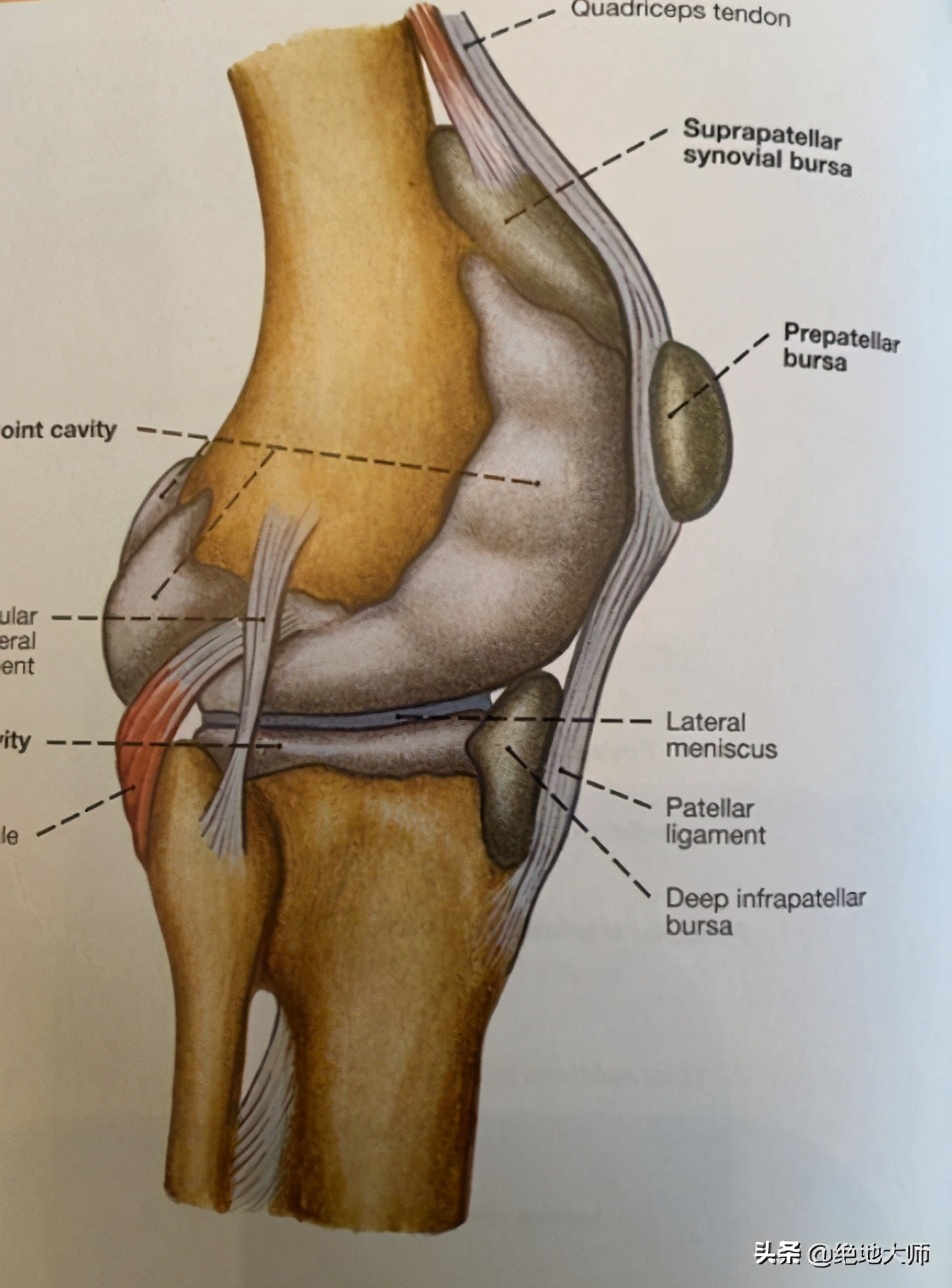

5. ANATOMY: PATELLA FEMORAL JOINT 解剖:髌股关节

PATELLA SITS BETWEEN THE FEMUR AND TIBIA 髌骨位于股骨和胫骨之间

FLOATS THE QUADRICEP BETWEEN THE QUADRICEP AND PATELLAR TENDON

在股四头肌和髌腱之间浮动股四头肌(皮下滑囊)

THE SMALLER THE PATELLA THE LESS FRICTON CREATED AND THE BETTER PERFORMANCE.

髌骨越小,产生的摩擦越小,表现更佳。

8. BURSA 滑囊

LUBRICANT 润滑

SUPRAPATELLAR 髌上

INFRAPATELLAR 髌下

PREPATELLAR 髌前

FRICTION, PRESSURE, OVERUSE CAUSE BURSITIS 摩擦、压力、过劳引起滑囊炎